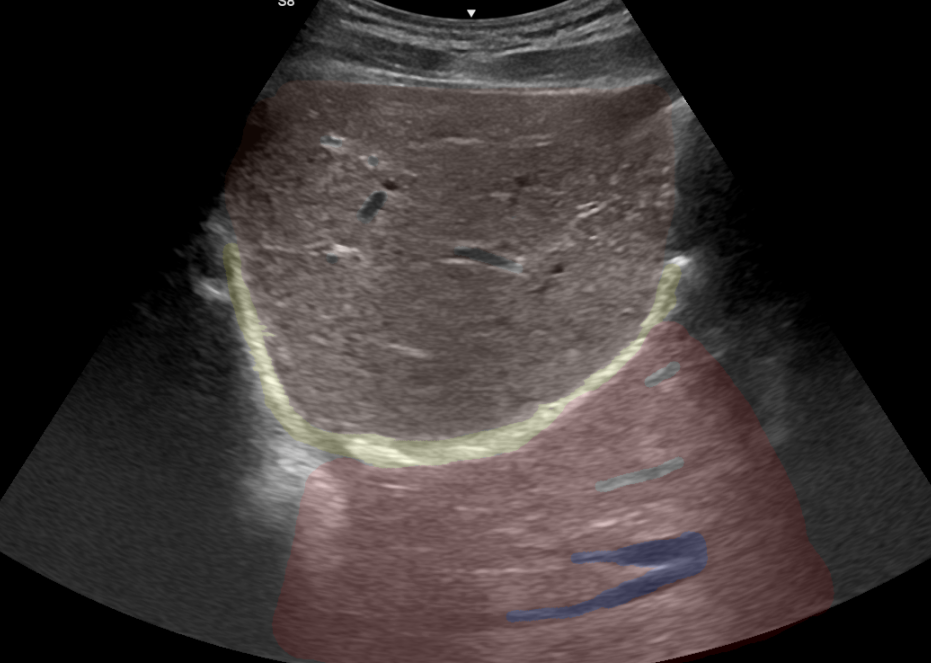

Imagen de adquaicion de un corte axial, con inclincacion craneal, en region subcostal derecha, con dirección hacia el hombro del paciente:

- Apreciamos el parenquima hepatico normal, como una estructura isoecoica homogenea, con vasos portales con refuerzo periportal habitual

- Se aprecia una imagen lineal hiperegogenica curvada, que genera un artefacto de reverberacion

- Tras la imagen , se aprecia parenquima hepático con estructuras vasculares tipicas de venas suprahepáticas

Un artefacto de espejo en ecografía ocurre cuando el haz de ultrasonido rebota en una superficie altamente reflectante, como una interfase entre dos medios con diferente impedancia acústica (por ejemplo, hueso y tejido blando). Este rebote produce una imagen especular de la estructura real, como si se estuviera viendo su reflejo en un espejo.